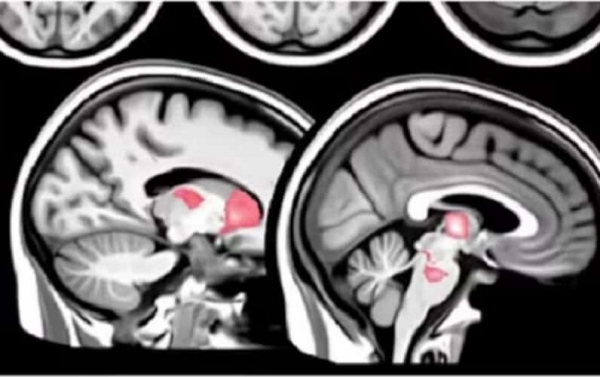

Nova študija razkriva, da "cepiva" mRNA povzročajo nenormalne imunske odzive, ki vodijo do dolgotrajne poškodbe možganov.

Skupina raziskovalcev je želela raziskati imunološke mehanizme, ki stojijo za vztrajnimi simptomi po cepljenju, zaradi povečanega števila poročil o poškodbah možganov pri cepljenih posameznikih.

Znanstveniki so ugotovili, da je "cepljena" kohorta trpela zaradi vztrajnih nevroloških simptomov in se soočala s tveganjem dolgotrajne škode.

Biopsije kože so potrdile zmanjšanje gostote majhnih živčnih vlaken, kar podpira povezavo z nevropatijo majhnih vlaken (SFN).